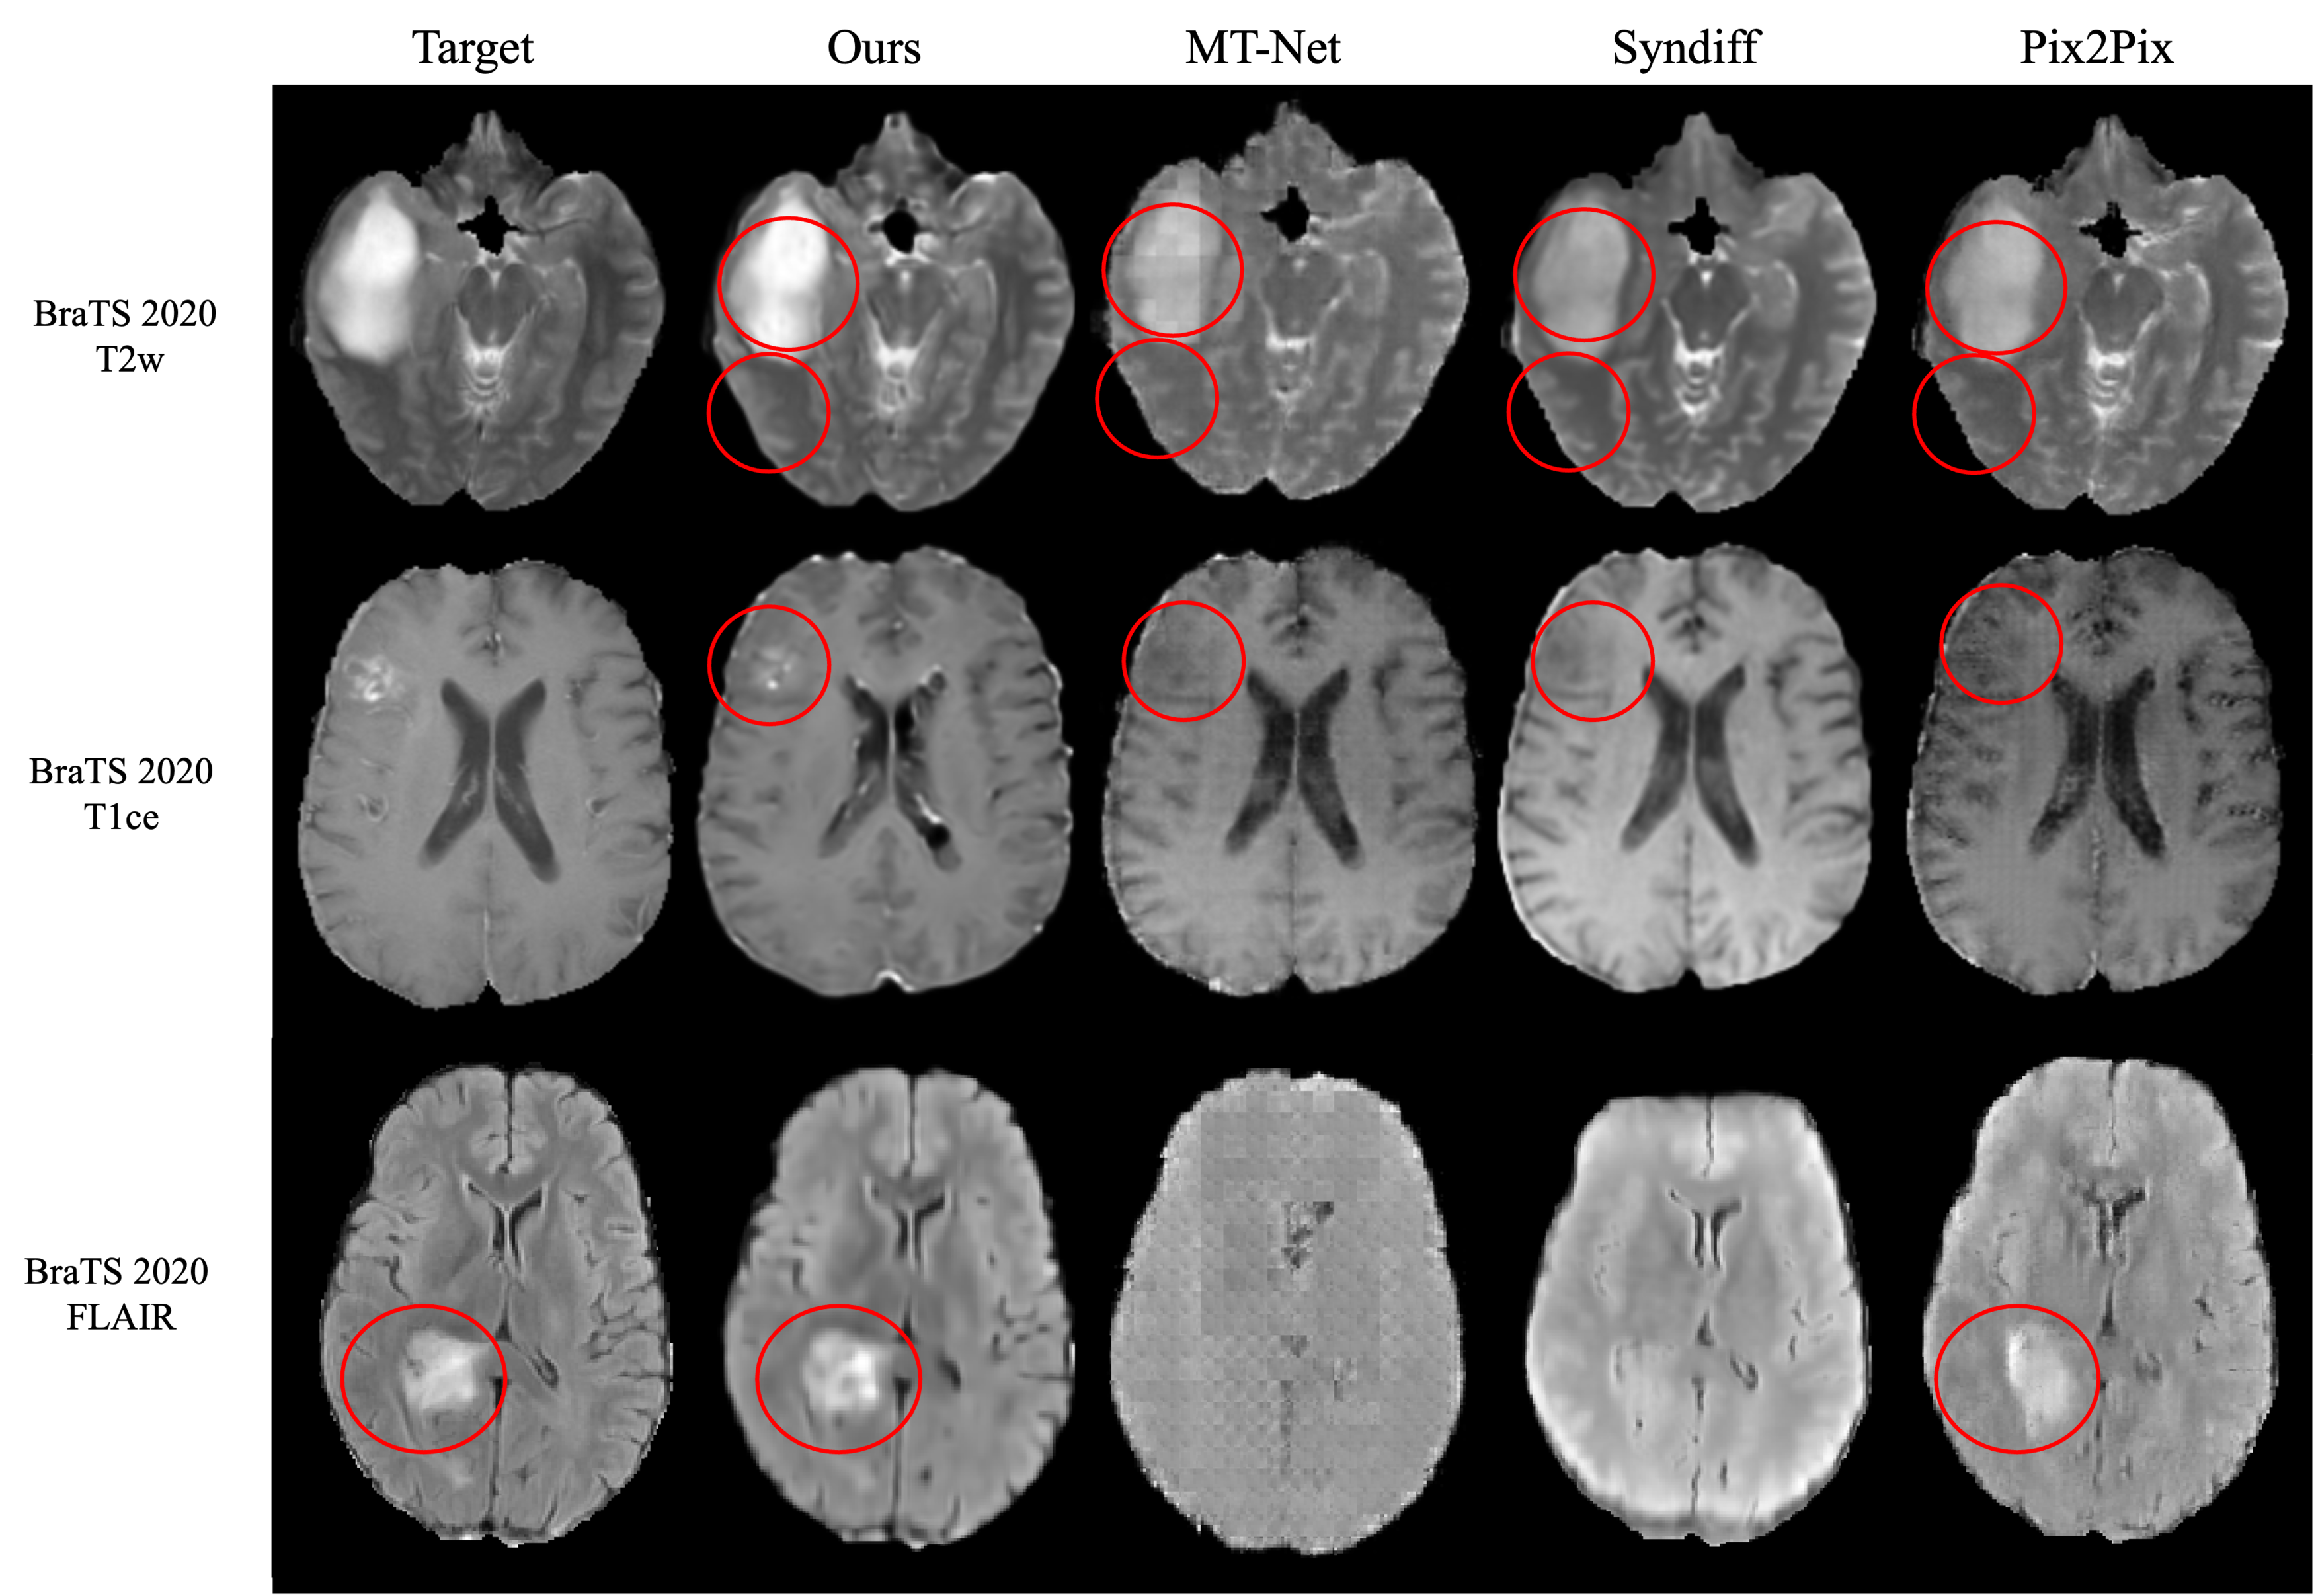

4.1.3 BraTS 2020

We used T1w, T2w, FLAIR, and T1ce from 25 low-grade glioma subjects (16 training, 9 test) across multiple cohorts. Samples were visually inspected for consistent image contrast and tissue characteristics, with background slices excluded from 70 extracted axial slices per subject.

5.1 Brain MR Image synthesis result

All experiments used T1w as the source modality, which serves as an optimal source sequence for synthesis due to its rapid acquisition time, clinical efficacy, and superior anatomical delineation [41]. The numbers in parentheses indicate the number of subjects used for training. For MT-Net, the format shows (pre-training subjects/fine-tuning subjects).

Our FGSB framework demonstrates exceptional data efficiency, achieving competitive or superior performance with dramatically fewer training subjects compared to existing methods(2, 3, 4, 5). Remarkably, FGSB trained on only 2-3 subjects consistently outperforms baseline methods trained on 10-25 subjects, while matching or exceeding state-of-the-art performance when using comparable training data. Our framework excels in preserving clinically essential structures, particularly lesions and white matter hyperintensities (WMHs), which are often lost or distorted by competing methods.